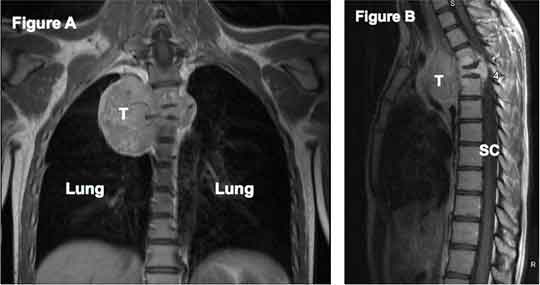

The advantages of using proton therapy to spare normal tissue extend to tumors unsuitable for surgery. In sarcomas arising from or near the spine, complete resection is often a challenge. Delivery of an adequate radiation dose is limited by surrounding radiation-sensitive normal tissues, including the spinal cord, intestines, lungs, heart, and kidneys. For example, in a tumor abutting the spinal cord, the clinician is often forced to balance inadequate local control with the unacceptable risk of serious side effects. The precise dose delivery of proton therapy is ideal for this situation.